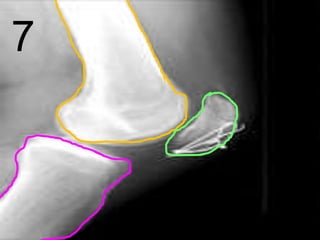

Note- Wearing high

heels can cause

many serious and

permanent health

problems to bones

and tendons.

Fibula

Tibia

Tarsals